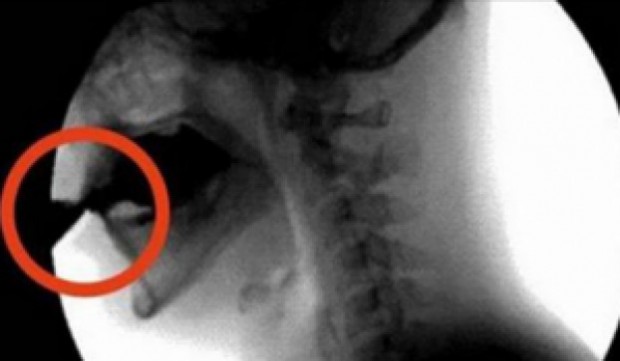

Soda može dovesti do osteoporoze

Sva gazirana pića sadrže fosfate ili fosforne kiseline koje im daju ukus i poboljšavaju njihov vijek trajanja. Fosforna kiselina postoji u mnogim cjelovitim namirnicama, ali previše može dovesti do srčanog i bolesti bubrega, gubitka mišićne mase, osteoporoze, a može ubrzati i proces starenja.

Previše fosforne kiseline u odnosu na unos kalcija može uzrokovati gubitak koštane mase, a kofein u gaziranim pićima može ometati apsorpciju kalcija. Gazirani sokovi smanjuju gustoću kostiju i povećavaju rizik od osteoporoze.